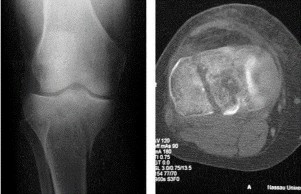

When treating a proximal tibia fracture, the surgeon decides to (1) use blocking screws in the proximal fragment, and (2) pick the intramedullary nail based on the location of the Herzog curve. Which of the following combinations will best prevent the classic deformity associated with this fracture? ](http://www.orthobullets.com/trauma/1062/proximal-third-tibia-fracture)